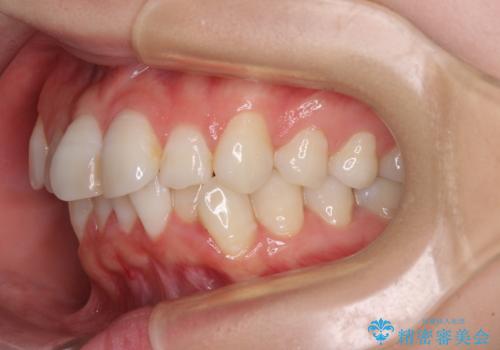

- 上下前歯のデコボコを改善したいとのことで来院された患者様です。

マウスピースを長時間装着し続ける自信はあまりないとのことでしたが、目立たない装置であれば頑張って装着するとのことで、インビザラインによる矯正治療を行うこととしました。

初めの1年くらいは何とか頑張って装着してくださいましたが、途中から変化をあまり感じられなくなり、日々の装着時間は徐々に短くなってしまいました。

前歯のデコボコはもっと改善できましたが、3年半が経過し、初診時と比べたら大幅に良くなったとのことで終了することとなりました。